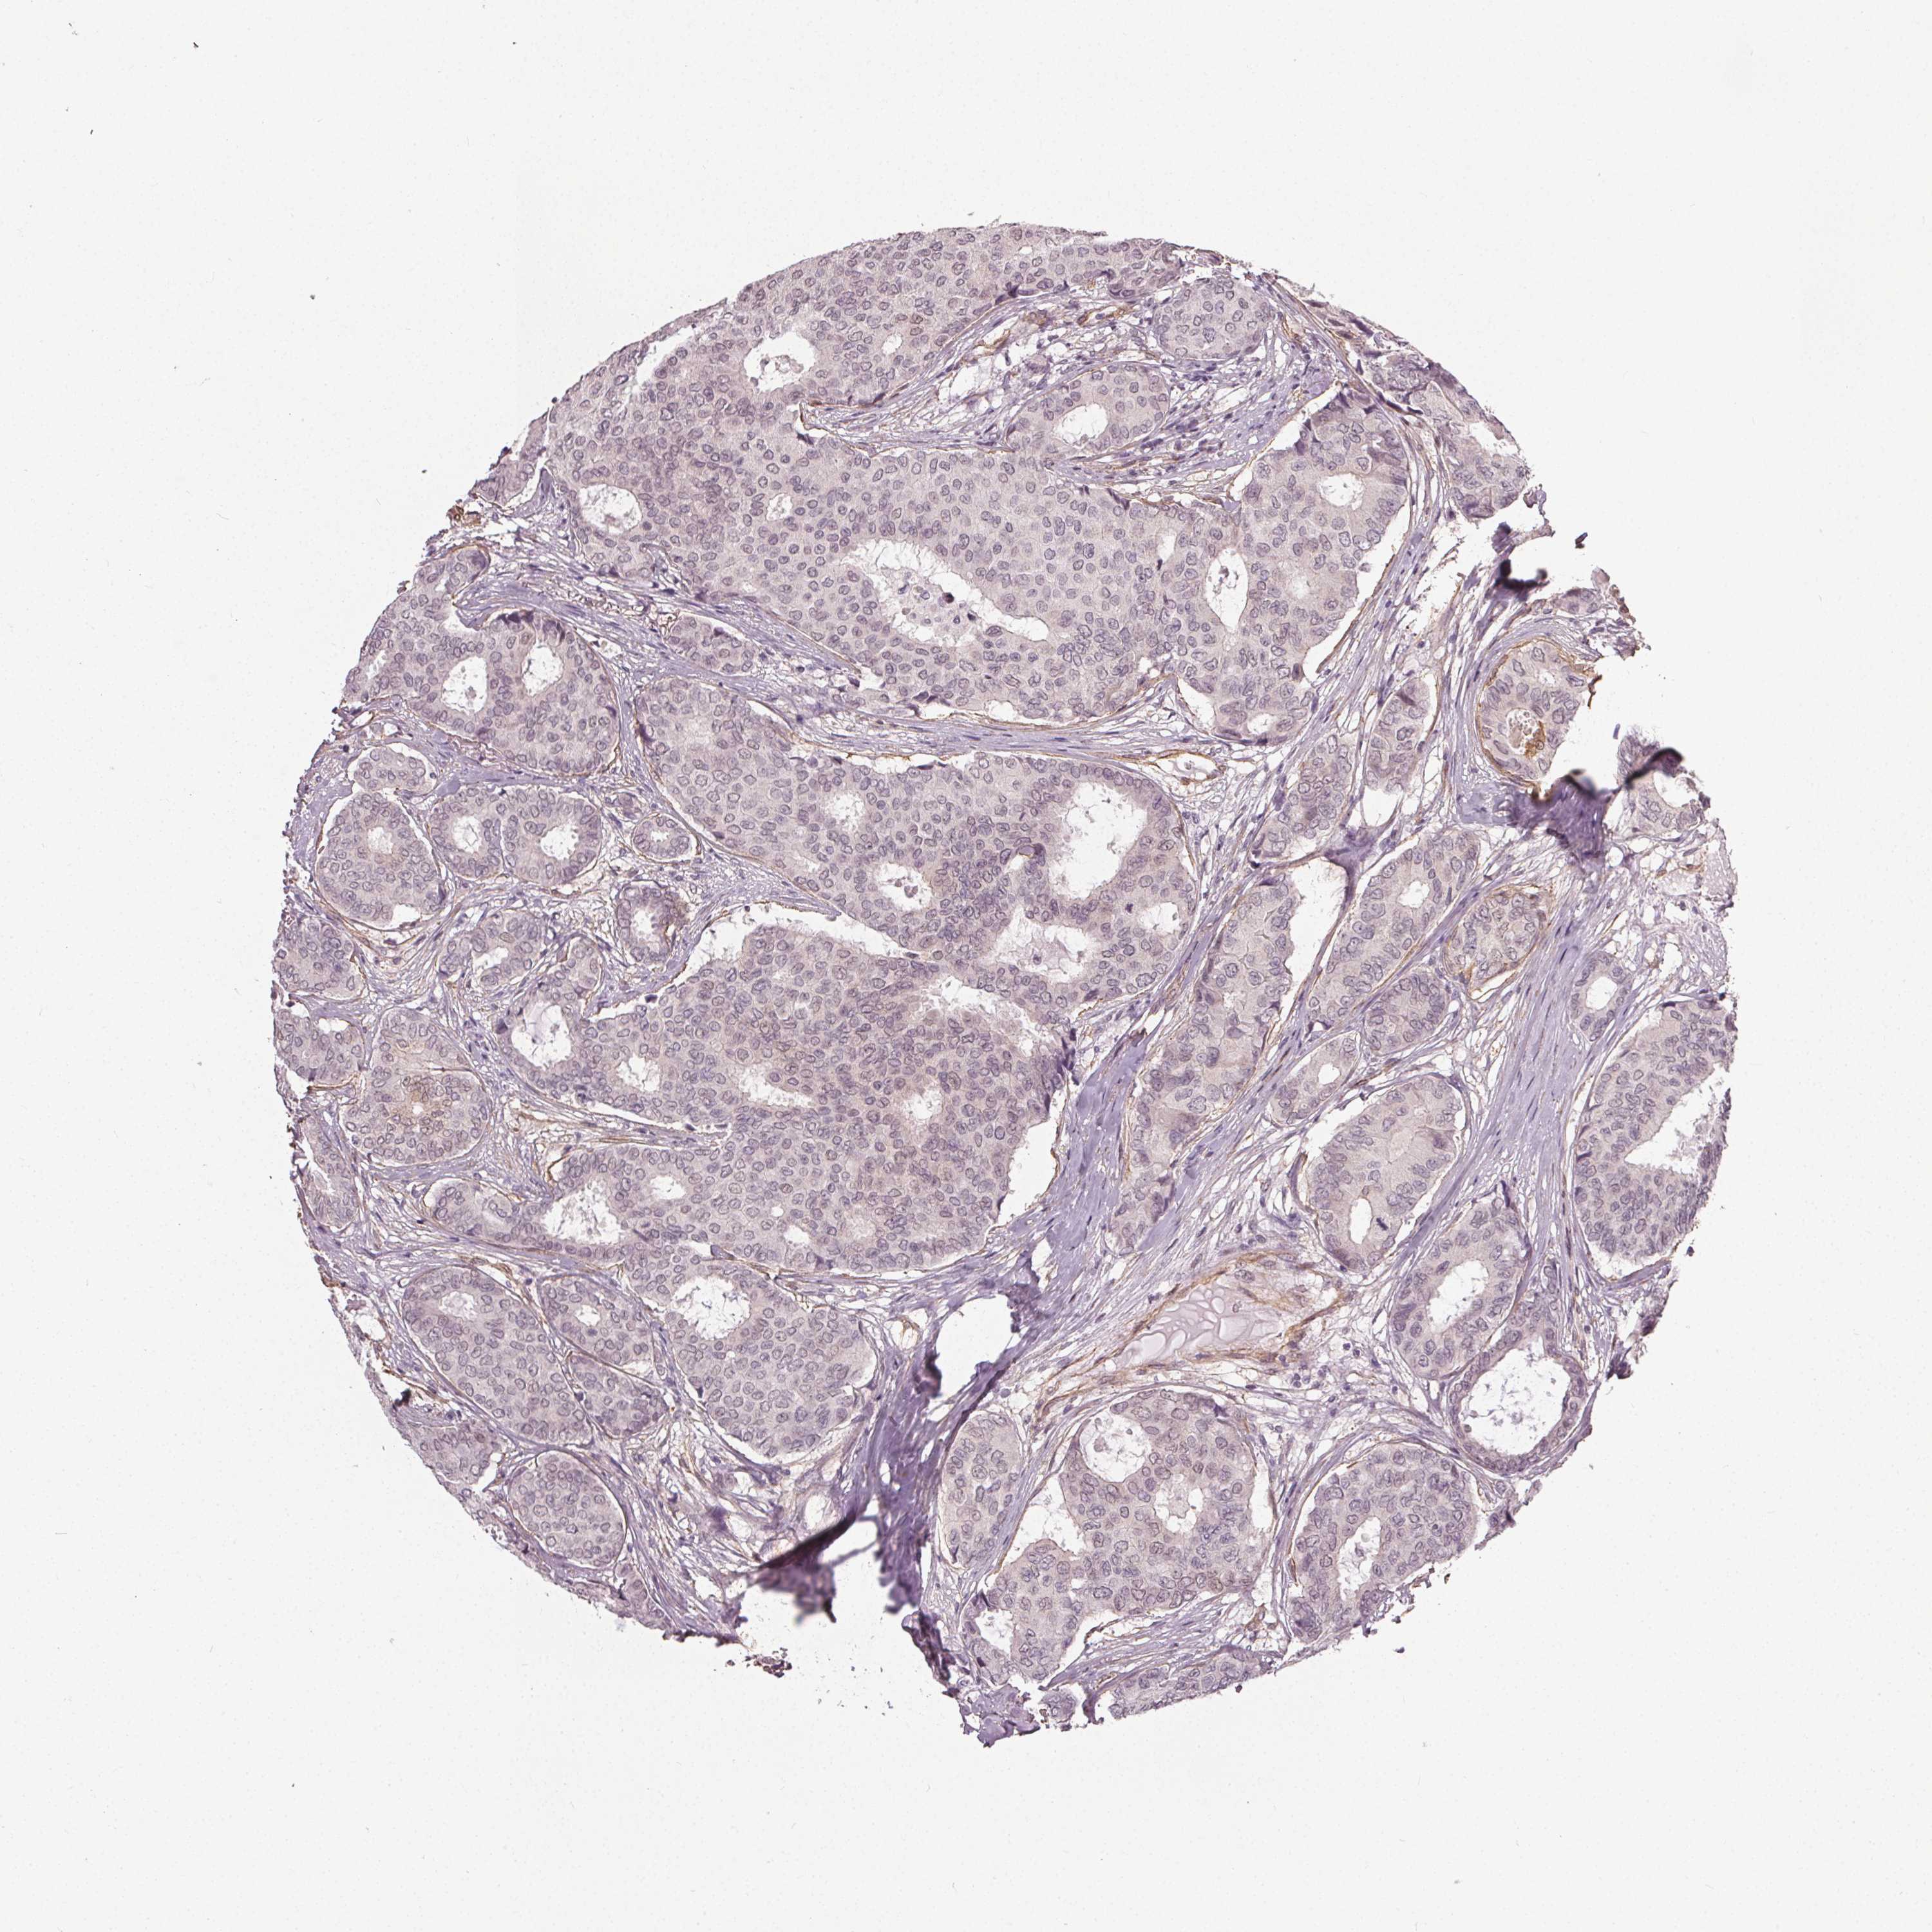

CANCER BREAST CANCER Show tissue menu

Breast cancer

Human cancer